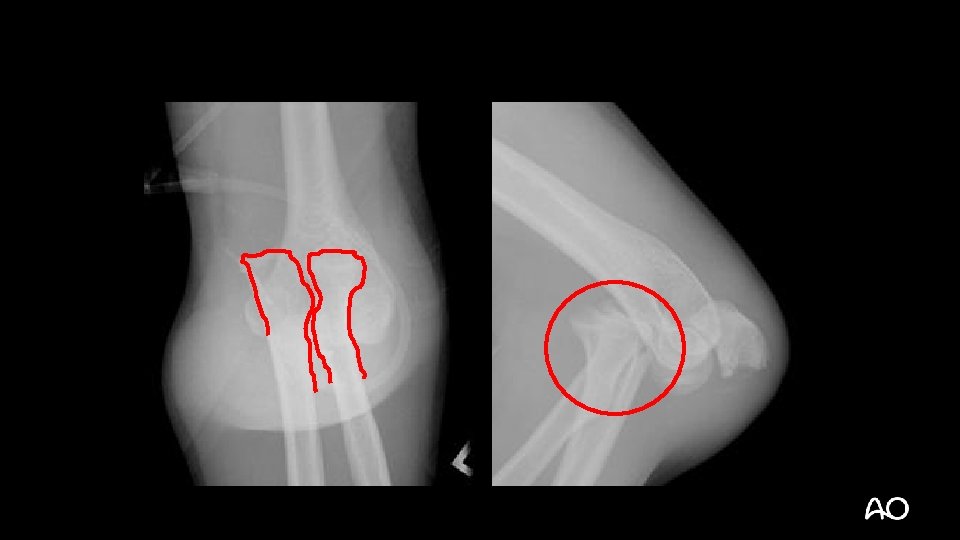

Varus posteromedial fracture dislocation • Recently described injury pattern • Failure to recognize can result in poor outcomes (arthrosis) • Easy to overlook (occasionally small coronoid fractures)

Varus posteromedial fracture dislocation Courtesy of David Ring • Stress views demonstrate that the LCL is ruptured and the elbow is unstable • Results can be poor without operative treatment

Varus posteromedial fracture dislocation—surgical tactic • Medial approach to elbow: • Split FCU, mobilize ulnar nerve • Sacrifice first motor branch? (Paulos et al [Surg Radiol Anat. 2015; 37: 1043– 1048]) • Dissect anterior to MCL • Buttress plating +/- lag screw(s) for coronoid • Stress elbow and repair LCL if instability remains: • Kocher approach

Varus posteromedial fracture dislocation